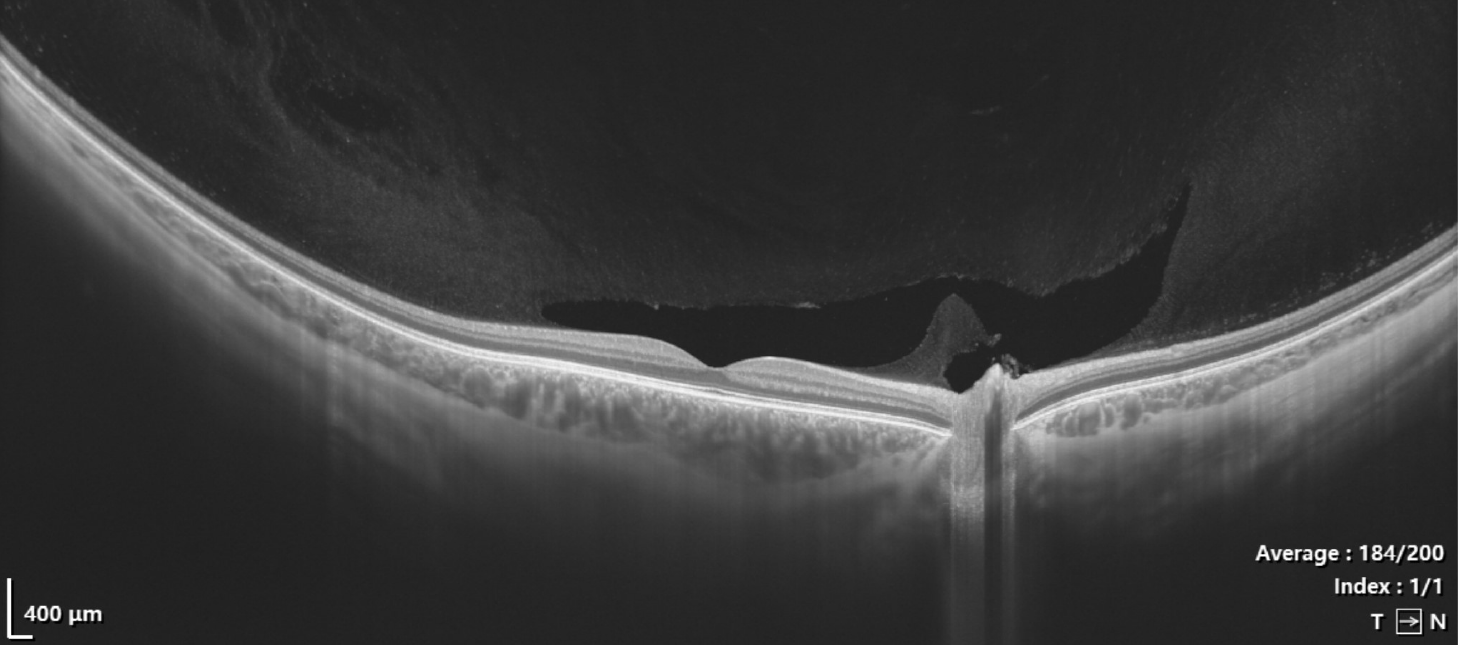

Optischer Kohärenztomographie (OCT) ist eine Bildgebungstechnologie,…

…welche zur Diagnose und Überwachung verschiedener Augenerkrankungen eingesetzt wird. Diese nicht-invasive Methode ermöglicht eine detaillierte Darstellung der Gewebestrukturen im Auge, insbesondere der Netzhautschichten.

Bei einer OCT wird ein spezieller Scanner verwendet, der mithilfe von Lichtwellen die Netzhaut und andere Augenstrukturen in hoher Auflösung abbilden kann. Das Licht wird in das Auge gesendet, wo es von den verschiedenen Gewebeschichten reflektiert wird. Die reflektierten Lichtwellen werden dann vom Scanner erfasst und in ein digitales 3D-Bild (Tomografie) umgewandelt. Das akustische Pendant dazu ist die Sonographie.

- Netzhauterkrankungen: Die OCT kann Veränderungen in den verschiedenen Schichten der Netzhaut identifizieren, was bei der Diagnose von Erkrankungen wie Makuladegeneration und diabetischer Retinopathie hilfreich ist.

- Grüner Star: Durch die Beurteilung des Zustands des Sehnervs und der retinalen Nervenfaserschicht kann die OCT helfen, das Glaukom frühzeitig zu erkennen und den Verlauf der Erkrankung zu überwachen.